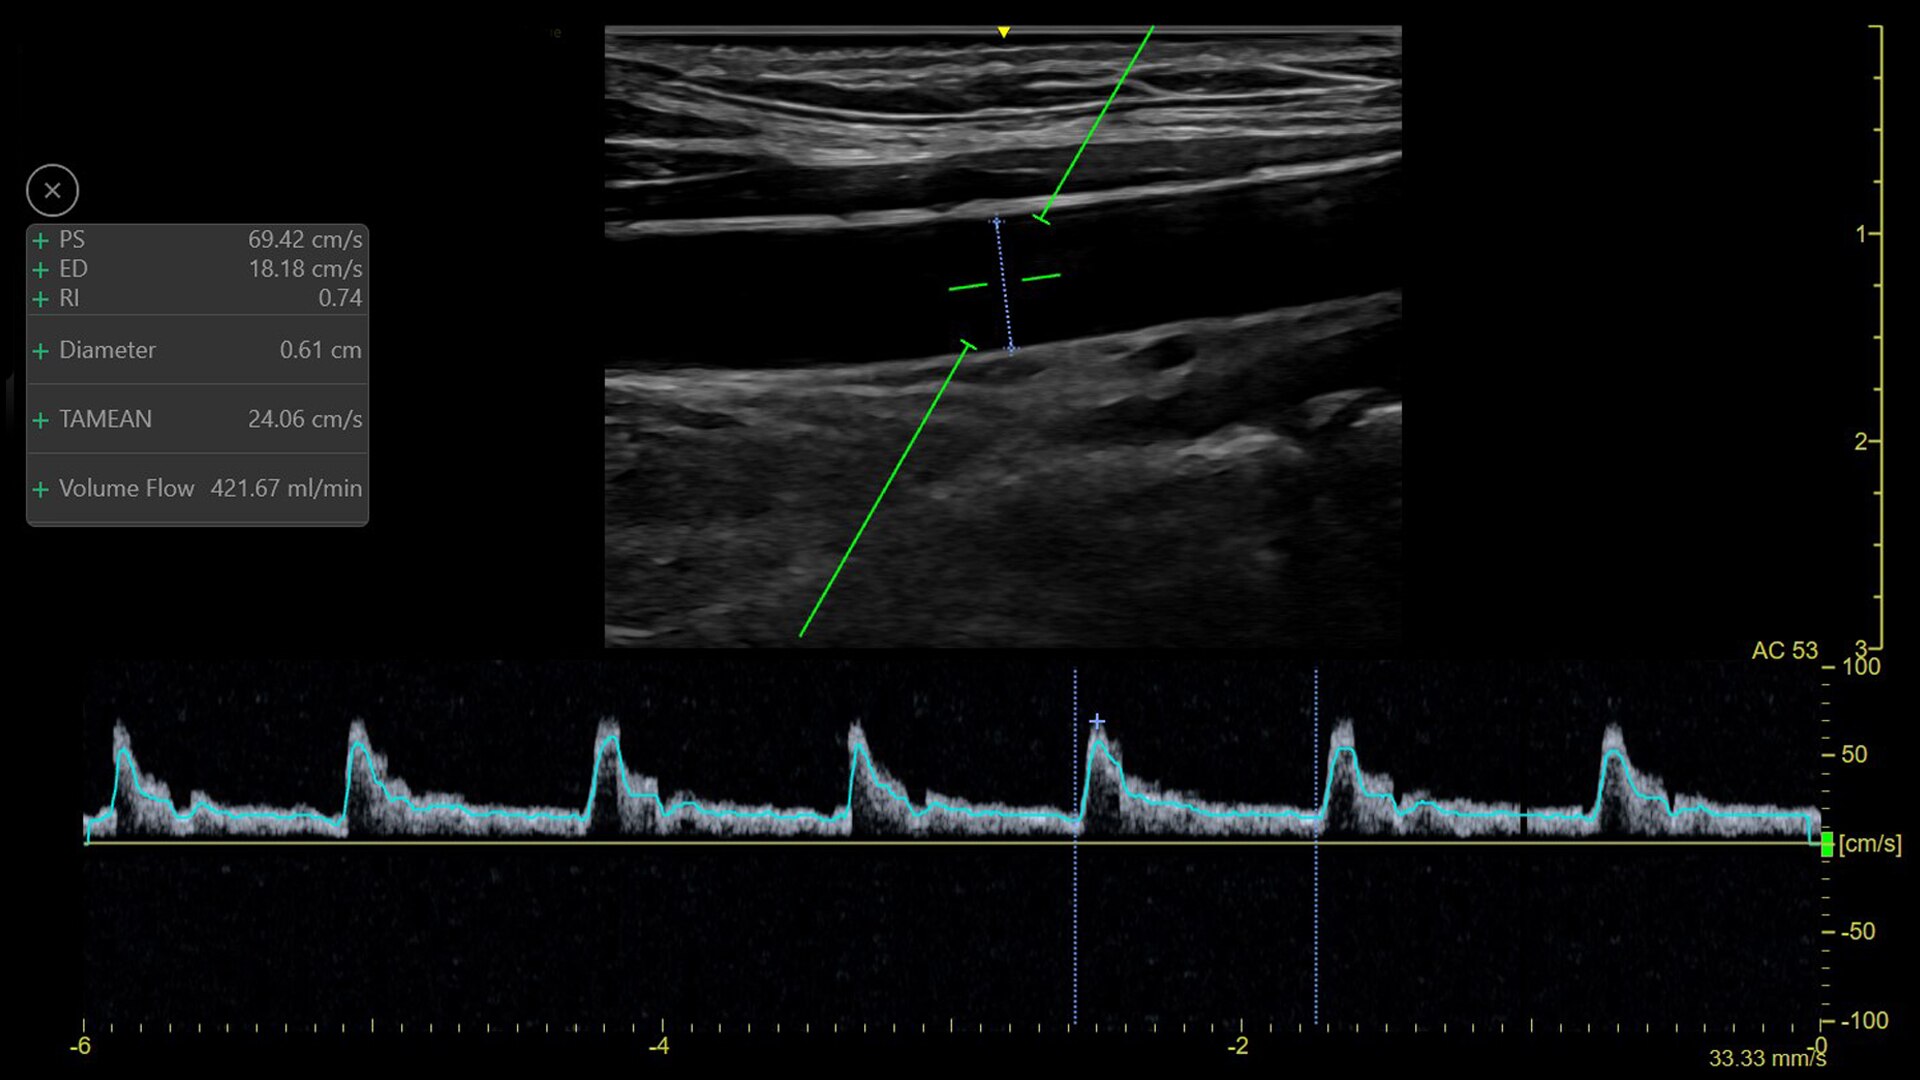

AUTO VOLUME FLOW

Auto measurement with Auto Volume Flow

Use the auto measurement to calculate the brachial or radial artery flow volume in real time for dialysis procedure preparation. Helps you calculate the arterial flow volume in real-time (based on vessel diameter and PW spectral doppler flow measurement).